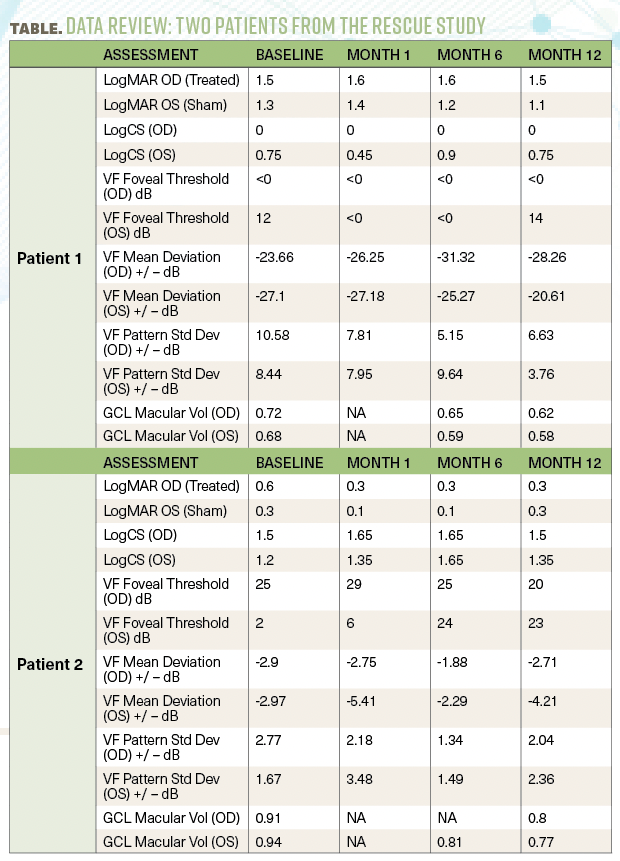

Table. Patients treated with an intravitreal injection of lenadogene nolparvovec (AAV2-ND4) at 9×1010 vg in one eye and a sham injection in the fellow eye.

The study under discussion included 2 patients from the RESCUE clinical study. The patients were treated within 6 months following bilateral visual loss with an intravitreal injection of lenadogene nolparvovec (AAV2-ND4) at 9×1010 vg in one eye and a sham injection in the fellow eye [Table].